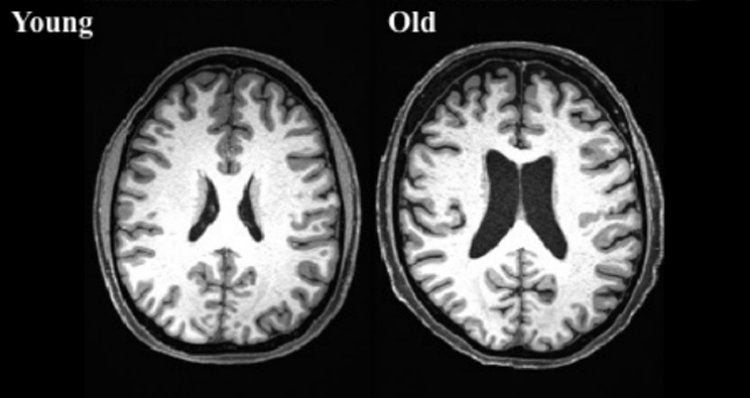

The brains of a 70-year-old and a 17-year-old can differ in several ways due to the natural aging process. Here are some general differences to consider: